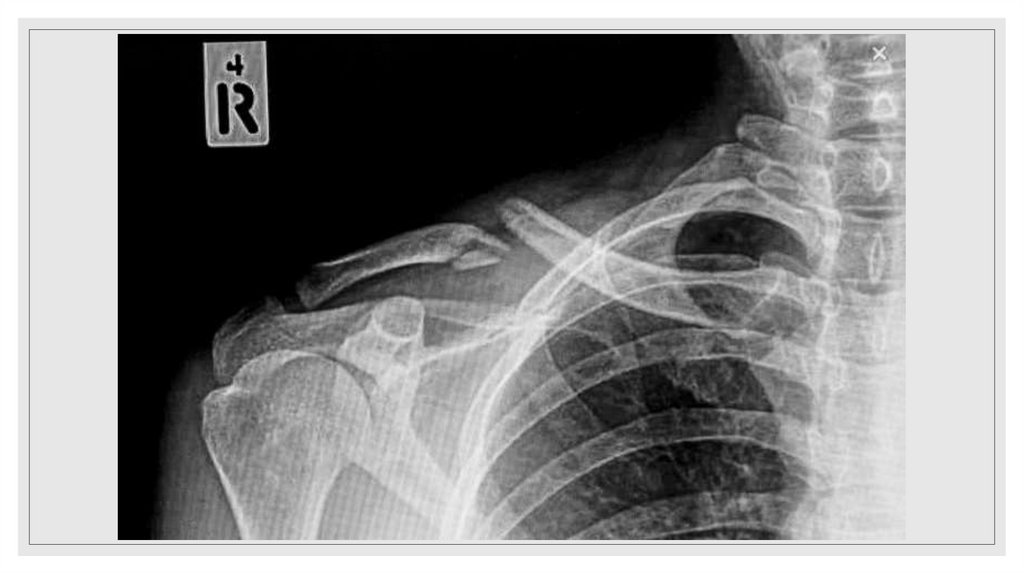

27. Переломы ключицы

Симптомы

деформации в области поврежденной

ключицы

локальная

болезненность

нарушения активных движений в плечевом

поясе.

Первая помощь

наложение

повязки

Дезо,

введение

обезболивающих средств.

Лечение

репозиция отломков фиксации с помощью

гипсовой повязки Дезо, ватно-марлевых

колец Дельбе (3-4 недели). Оперативное

лечение показано при открытых переломах,

интерпозиции мягких тканей.